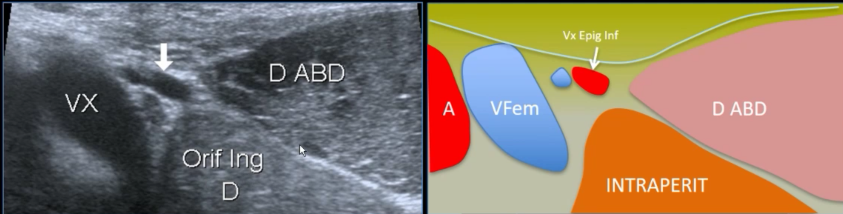

Hernies inguinales

Technique

- Sonde pointe un peu vers le nombril

- Aligner VX fémoraux - VX epigastriques - Droit abdomen

- Repères anatomiques:

- Vx épigastriques inférieurs (les suivre depuis en haut si doute) = 1 artère 2 veines

- Cordon spermatique

- Muscle droit de l’abdomen

Coupe standard

Ne pas confondre avec le cordon spermatique qui part entre deux

En vrai il y a 2 veines épigastriques inf

Hernie inguinale indirecte

Hernie inguinale directe